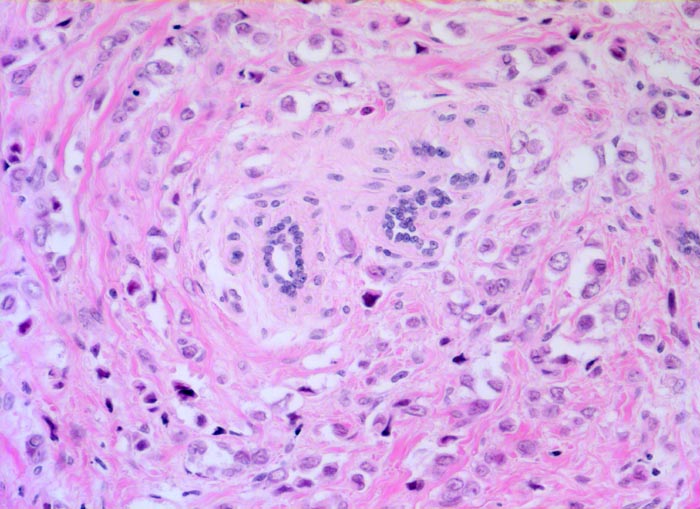

PathoPic ID 5244 - Invasives lobuläres Mammakarzinom

Invasives lobuläres Mammakarzinom

maligner Tumor

Mamma

Die recht monomorphen und nicht sehr grossen

Tumorzellen sind in einreihigen Ketten konzentrisch um ein

vorbestehendes Läppchen angeordnet.

Mammographisch suspekter Herd im äusseren oberen Quadranten. Probeexzision.

Histologie

200

42